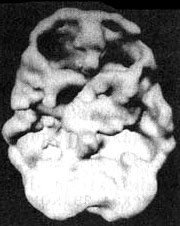

Мозг человека, употребляющего много кофеина и никотина

Трехмерное изображение поверхности, вид снизу. Обратите внимание на выраженное общее снижение активности, особенно в префронтальной коре и височных долях.

Как-то ко мне приехал знакомый — успешный бизнесмен. Он рассказал, что в последнее время ему трудно сосредоточиться, у него мало сил. Я знал, что в день он выпивает минимум по три кружки кофе и выкуривает по три пачки сигарет. Долгое время я думал, что у него синдром дефицита внимания (он плохо учился в школе, совершал импульсивные поступки и не мог долго сидеть на месте), и что он использовал никотин и кофеин в качестве стимулятора мозговой деятельности. Он был генеральным директором чрезвычайно успешной корпорации и не привык слушать чужие советы. Я рассказал ему про СДВ и сказал, что хватит заниматься псевдолечением при помощи лошадиных доз кофе и сигарет. Вместо этого лучше было бы заняться непосредственно лечением СДВ. Его первой реакцией был вопрос: нет ли у нас какого-нибудь природного средства для лечения СДВ, потому что ему не хочется принимать лекарства. Слегка изумленный, я ответил: «Так вы же принимаете целых два — никотин и кофеин, и они вполне могут вас уморить! Я же прописываю лекарство, которое действует гораздо эффективнее и при этом, если его принимают правильно, никого не убивает!»

Я предложил ему провести сканирование SPECT, чтобы с его помощью точнее определить состояние мозга. Кроме того, наглядные изображения могут стать лучшим аргументом против курения и кофе. Результаты сканирования стали неприятной неожиданностью даже для меня. Активность была заметно снижена по всей поверхности коры, и особенно в области префронтальной коры и височных долей. Я сказал своему знакомому, что ему надо найти другой стимулятор работы мозга, помимо кофе и никотина. В противном случае может получиться так, что он попросту окажется не в состоянии в полной мере вкусить радость успеха — у него не останется на это мозга. На протяжении нескольких недель он держался, но затем вновь вернулся к своим привычкам. И вот мне интересно: или сниженная активность височных долей «помогла» ему забыть то, что он увидел на изображениях SPECT, или очень низкая активность префронтальной коры не дает ему возможности в должной мере управлять собственными импульсами. И хотя я рекомендовал ему попробовать препарат, стимулирующий активность мозга (Ritalin или Adderall), он настоял на том, что хотел бы вылечить свой СДВ «естественным путем».